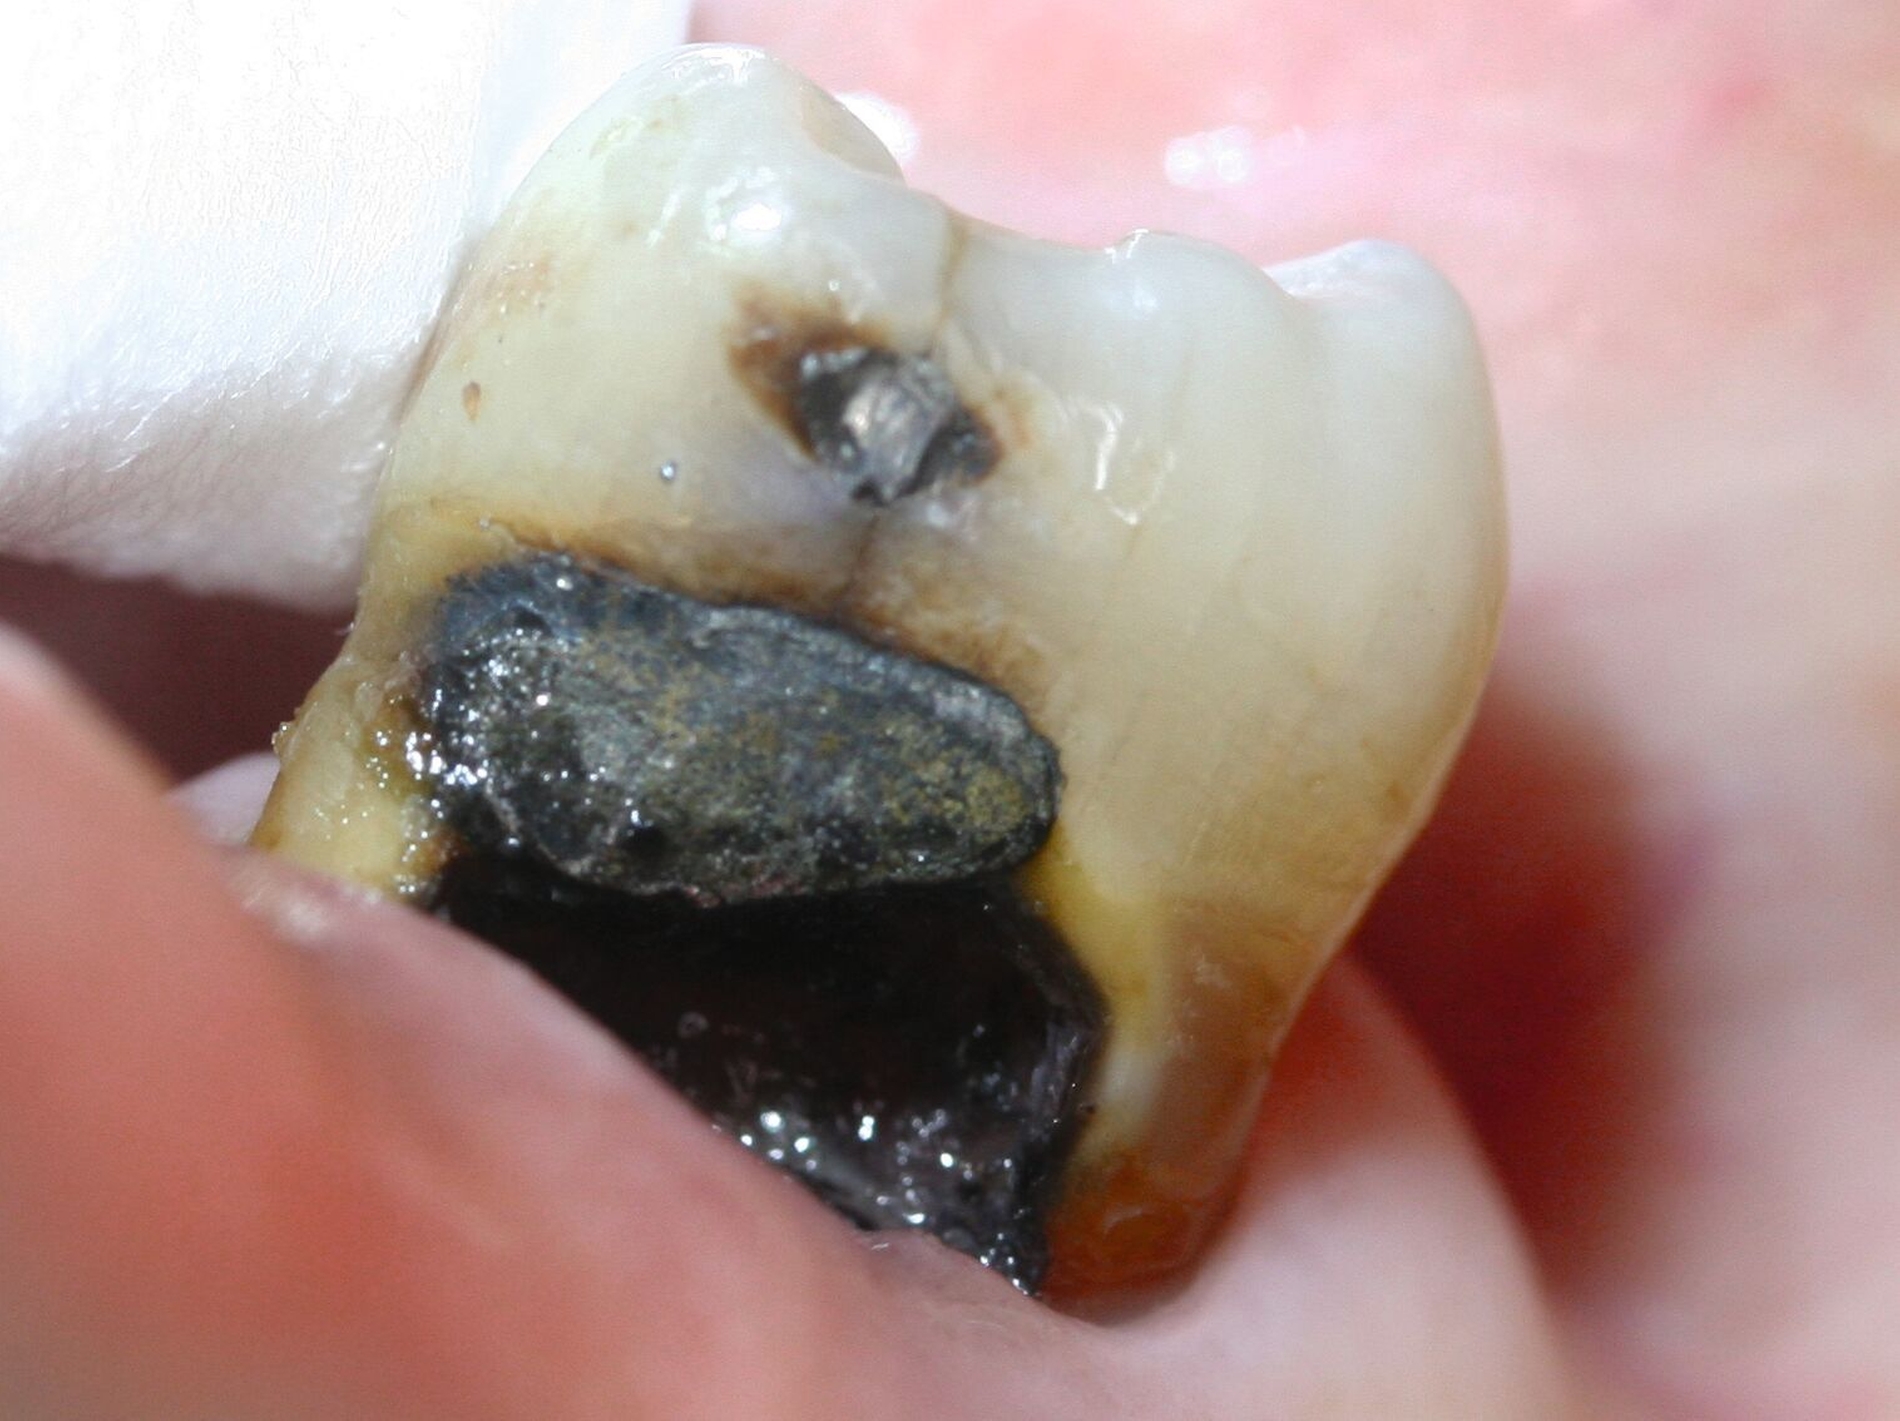

Mit Silberdiaminfluorid gegen Wurzelkaries

SDF hat sich sowohl bei der Prävention als auch bei der Behandlung von Wurzelkaries bei Senioren als wirksam erwiesen (Abbildung 6). Systematische Übersichtsarbeiten zeigen, dass 38-prozentiges SDF das Auftreten neuer kariöser Läsionen auf freiliegenden Wurzeloberflächen signifikant reduziert und bestehende Läsionen arretiert. Eine jährliche Anwendung von 38-prozentiger SDF-Lösung reduziert das Auftreten neuer Wurzelkaries um 50 bis 68 Prozent und zeigt eine noch größere Effektivität über längere Zeiträume [Chan et al., 2022; Hendre et al., 2017].